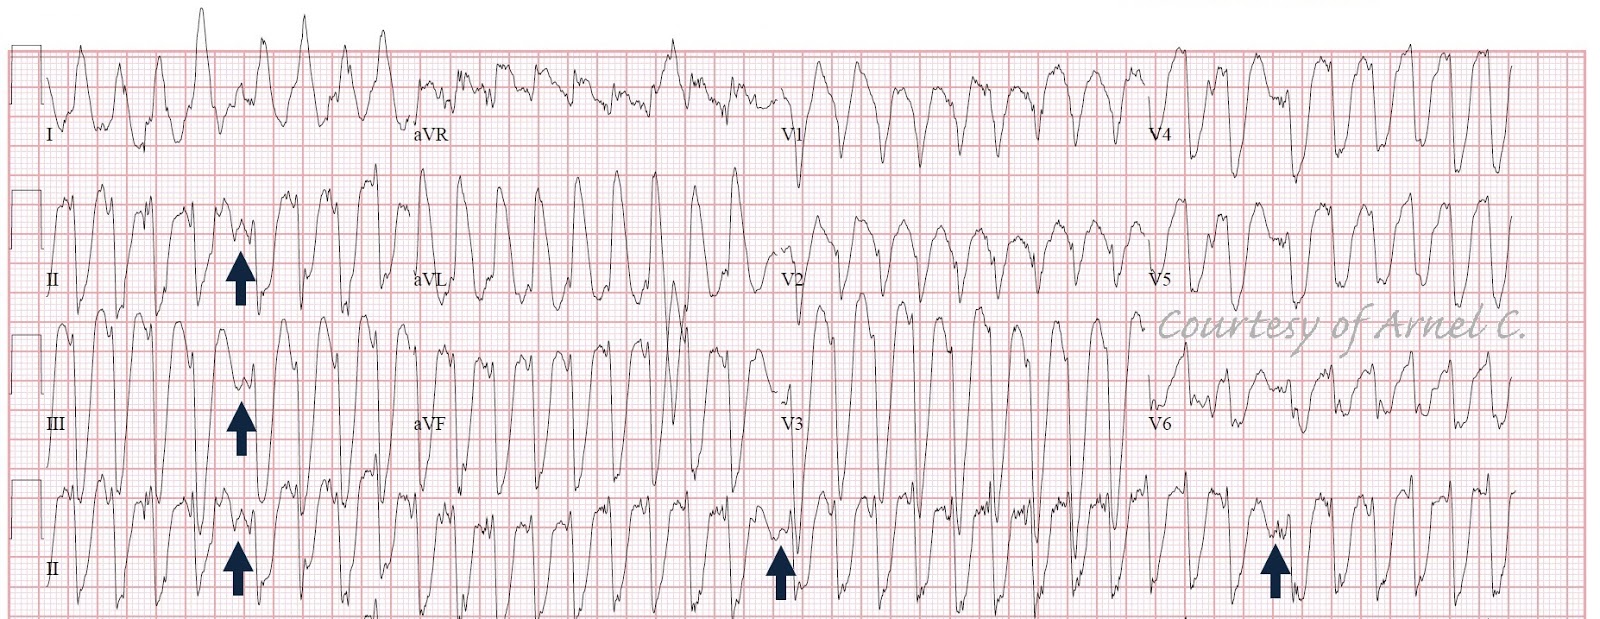

Ecg Quiz Very Wide And Very Fast